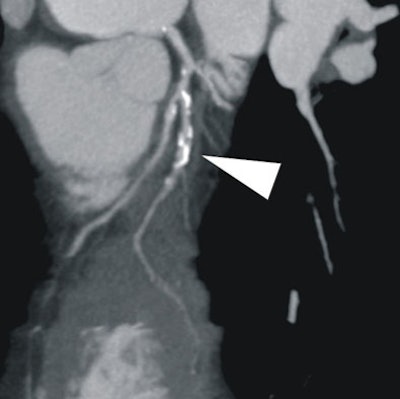

| In a 64-year-old man with chest pain, conventional catheter angiography confirmed the coronary CTA findings, and described a 50% ostial stenosis with diffuse disease throughout the vessel and a discrete 90% stenosis in the mid right circumflex artery (RCA) (arrows). |